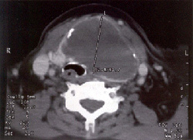

TAC cervical, Quiste tiroideo de gran tamaño, que ocupa todo el lóbulo tiroideo izquierdo, comprime la traquea y el esófago ( que introduce en la pared posterior de la traquea ), su prolongación inferior se introducía en mediastino, preciso hemitiroidectomia izquierda - Quistes paratiroideos